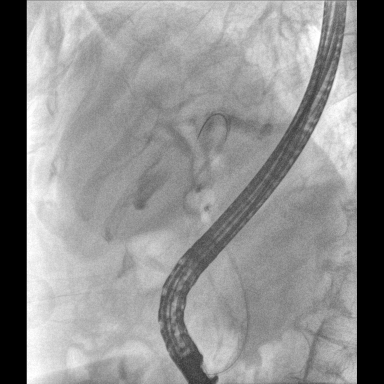

具備血管造影及數(shù)字減影(DSA)、路徑圖(Road-map)、透視、攝影等功能。 廣泛適用于介入科、血管外科、腫瘤科、消化內(nèi)科及骨科等多個(gè)臨床科室,典型應(yīng)用包括:TACE(肝腫瘤栓塞與化療灌注術(shù))、心臟起搏器置入術(shù)、四肢動(dòng)脈造影術(shù)、下肢靜脈濾器置入術(shù)、ERCP(經(jīng)內(nèi)鏡逆行胰膽管造影術(shù))等。

預(yù)留高壓注射器聯(lián)動(dòng)接口,C形臂開始透視時(shí),高壓注射器自動(dòng)注入造影劑,提高術(shù)中造影減影效率,減少醫(yī)師手推造影劑所受到的輻射暴露劑量。